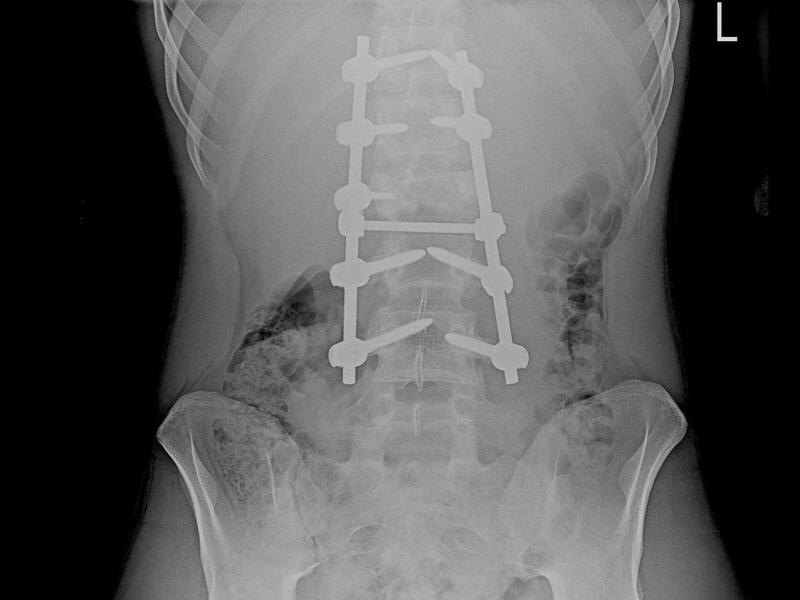

Тогда его срочно увезли в ближайшую райбольницу, а затем в воронежскую больницу скорой медицинской помощи №1. Медики выявили закрытый нестабильный компрессионно-оскольчатый перелом одного позвонка; переломы тела и поперечных отростков двух других позвонков; множественные переломы рёбер с двух сторон; двусторонний малый пневмоторакс (скопление воздуха или газов в плевральной полости, которое приводит к сдавливанию лёгкого, из-за чего оно не может полностью расправиться при вдохе); ушиб обоих лёгких.

В БСМП №1 подростку провели сложнейшую операцию, выполнив стабилизацию пяти позвонков с помощью специальной металлической конструкции из титановых винтов и стержней, удалили задние и передние структуры позвонка из заднебокового доступа.